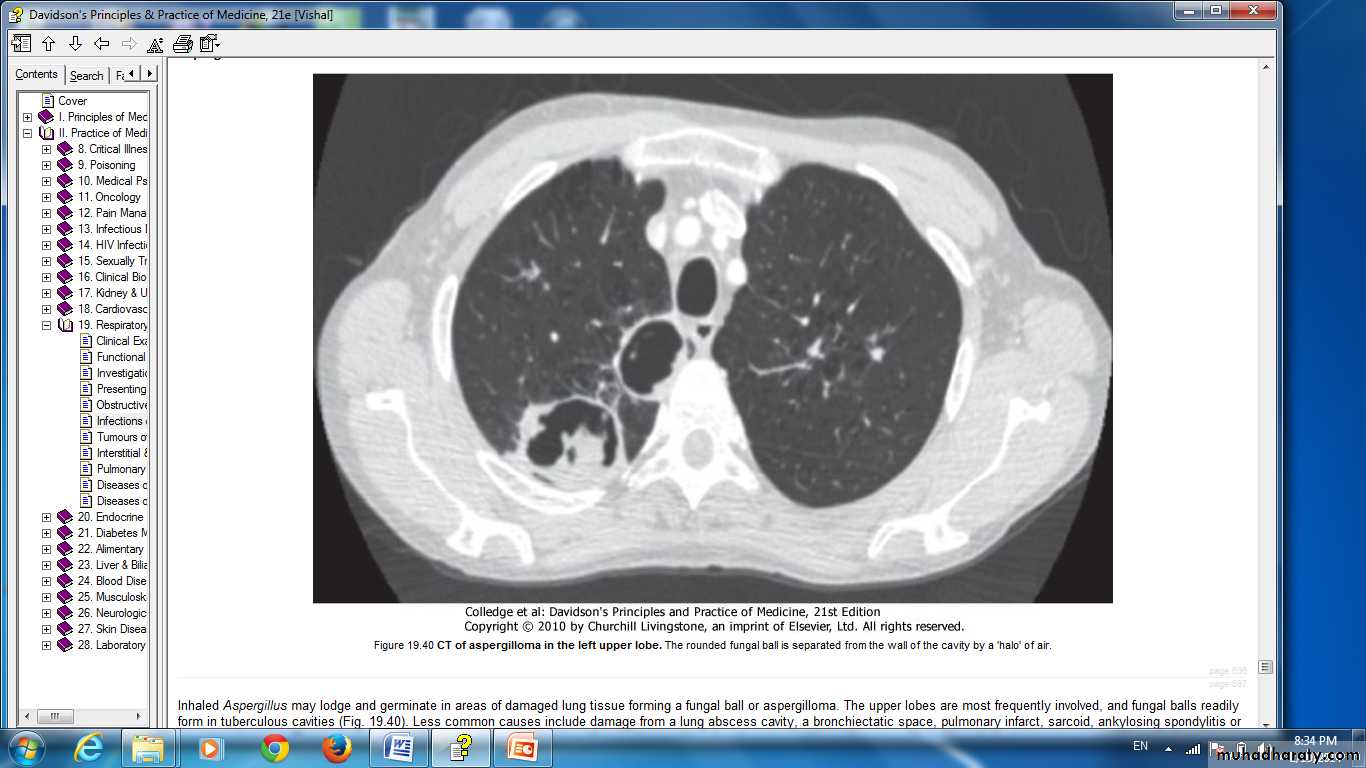

Inhaled Aspergillus may lodge and germinate in areas of damaged lung tissuea fungal ball or aspergilloma.

The upper lobes.

Cavities of any cause.

The 'complex aspergilloma'

presence of multiple aspergilloma cavities.